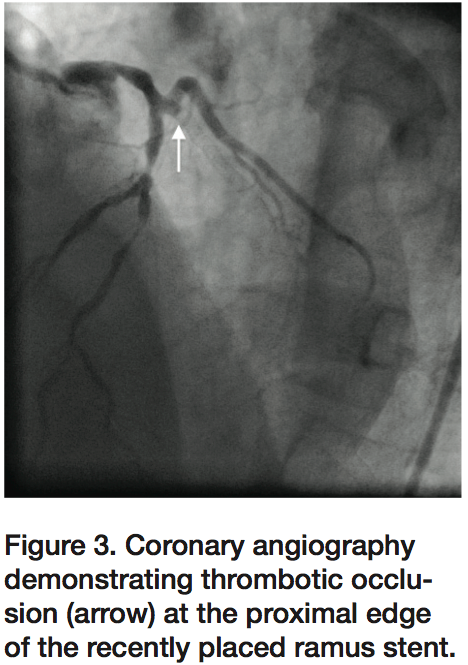

Approximately 25 minutes post-procedure, the patient developed severe chest pressure with lateral ST elevations. The patient was taken back emergently to the catheterization laboratory, where angiography demonstrated 100% thrombotic occlusion of the RI at the proximal edge of the recently placed stent (Figure 3). The patient was re-bolused with bivalirudin, followed by infusion and activated clotting time (ACT) after bivalirudin administration was confirmed to be 397 seconds. Laser atherectomy was performed using a 0.9 mm excimer laser